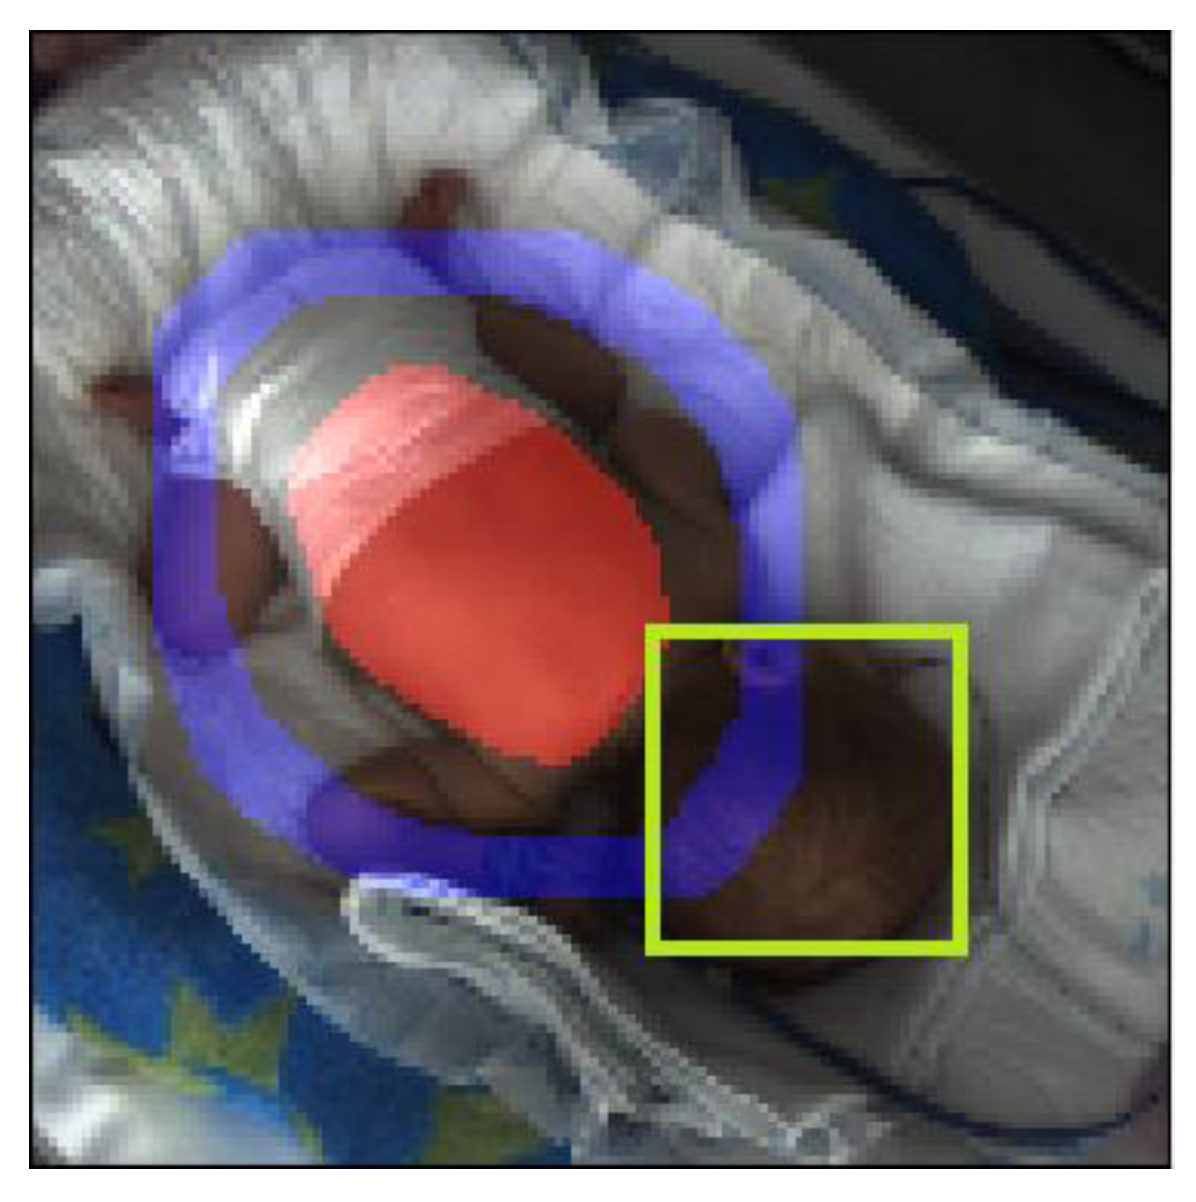

The feature extraction module started with the detection of different regions of interest (ROI). We started from the assumption that there were regions in the image that carried special information, separate from the other areas that could be useful to us in classifying activity phases (Figure 3). The examples are as follows:

• A ring around the baby’s abdomen including the limbs;

• The infant’s face.

Finding pixels for these regions was a segmentation task. Except for the baby’s entire body, we segmented each area and collected movement, color and intensity information from them separately.

It was easy to conclude that these regions listed above carried specific information. The need to use the full picture was trivial. The abdominal region is the area where respiration can be observed, which is an important descriptor for determining activity phases [8,9,10]. The “ring around the baby’s abdomen” was also important: this area was likely to include the majority of the limbs on the image, if the parameters were chosen correctly, and so we can extract information about the limb movements of the baby. The last region was the baby’s face, giving us information about whether the baby’s eyes are open or not, which is also an important descriptor.

Figure 3. Regions that may be of key importance in determining activity phases. These are used as different ROIs in feature extraction.